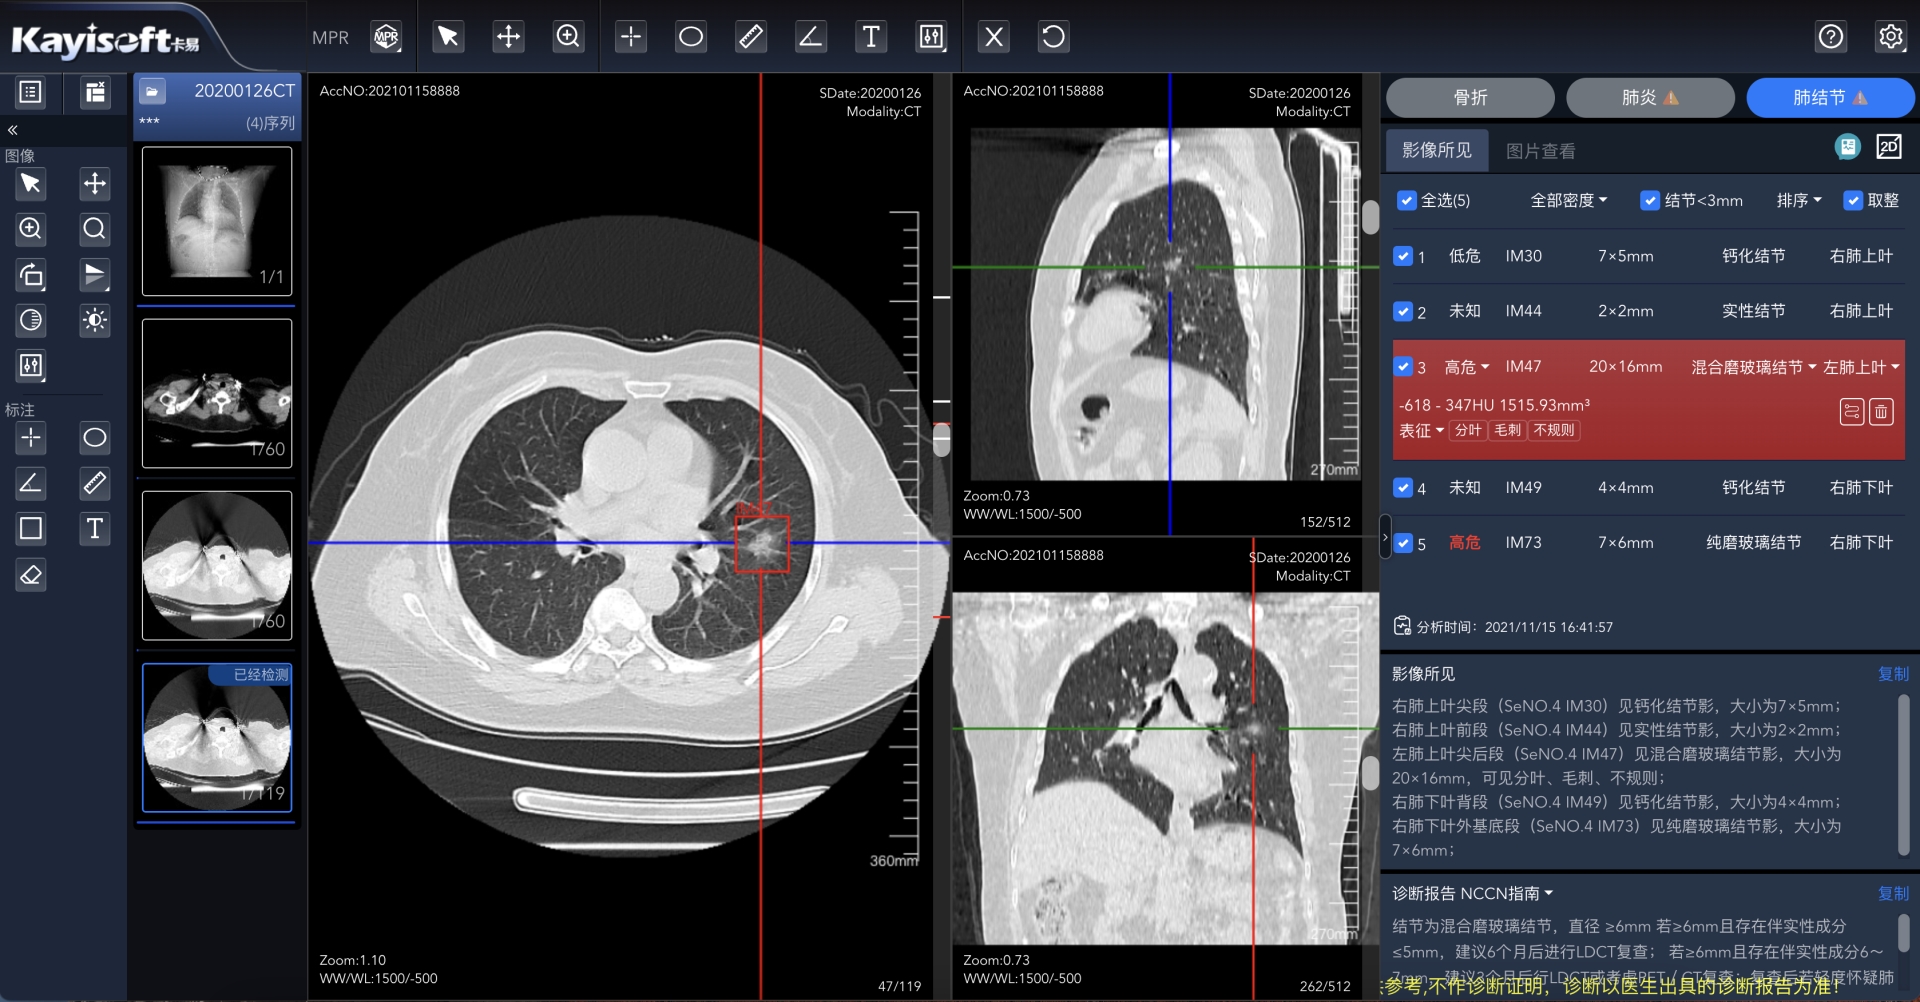

该产品通过温州市医学影像云平台完成区域医疗影像数据云化管理数据统一采集,实现以数据为基础,结合AI 分析服务肺结节智能标注,在短时间内分析完成并生成“AI 结构化报告”和“指南参考”来协助诊断医生参考,提高工作效率。截止目前,调阅数据量超过242万例。